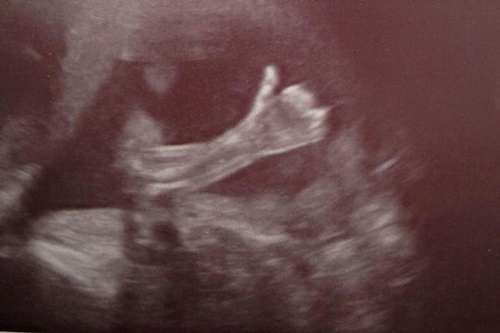

Hình ảnh thai nhi với ngón tay cái giơ lên như báo hiệu cho bố mẹ tình trạng của mình vẫn tốt khi nằm trong bụng mẹ được lan truyền nhanh chóng trên các trang mạng.

Bé Lochlan Schofield đã trở nên nổi tiếng khi vẫn nằm trong bụng mẹ sau khi hình ảnh siêu âm của bé với ngón tay cái giơ lên được bố mẹ chia sẻ trên mạng xã hội. Hình ảnh này như một thông điệp bé muốn gửi đến bố mẹ là: “Con ở trong này đang rất ổn.”

Hình ảnh được chụp lại trong lần siêu âm thai 4D tuần thứ 20. Ngay sau khi được cặp đôi Cheryl Stevenson và Paul Schofield đăng tải, hình ảnh này đã lan truyền chóng mặt như một loại virus, thậm chí còn được nhiều người nổi tiếng như ngôi sao truyền hình thực tế Bristol Palin hay con gái của chính trị gia Sarah Palin chia sẻ lại.

Chia sẻ về hình ảnh siêu âm thai đặc biệt này, chị Cha Paul nói: “Vào thời điểm khi có hình ảnh siêu âm này, cả bác sĩ, nữ hộ sinh, tôi và chồng đều cười lớn. Đó là hình ảnh thật đáng yêu của bé. Chúng tôi cũng sẽ lưu giữ hình ảnh này để làm kỷ niệm.”

“Đặc biệt hơn cả là hình ảnh này đã nhận được rất nhiều lượt like trên Twitter và facebook từ rất nhiều bạn bè trên toàn thế giới, kể cả những người không quen biết gia đình tôi. Vậy là em bé đã nổi tiếng từ khi còn chưa ra đời.”, ông bố trẻ chia sẻ thêm.

Bố mẹ của em bé cũng cho biết, họ không hiểu nổi tại sao bé có thể giơ được ngón tay như thế khi mới 20 tuần thai. Hiện tại, vì còn nhỏ nên tay Lochlan không thể thực hiện được động tác đó nhưng họ sẽ huấn luyện để con có thể giơ ngón tay cái với biểu tượng "đang rất ổn" được sớm nhất.